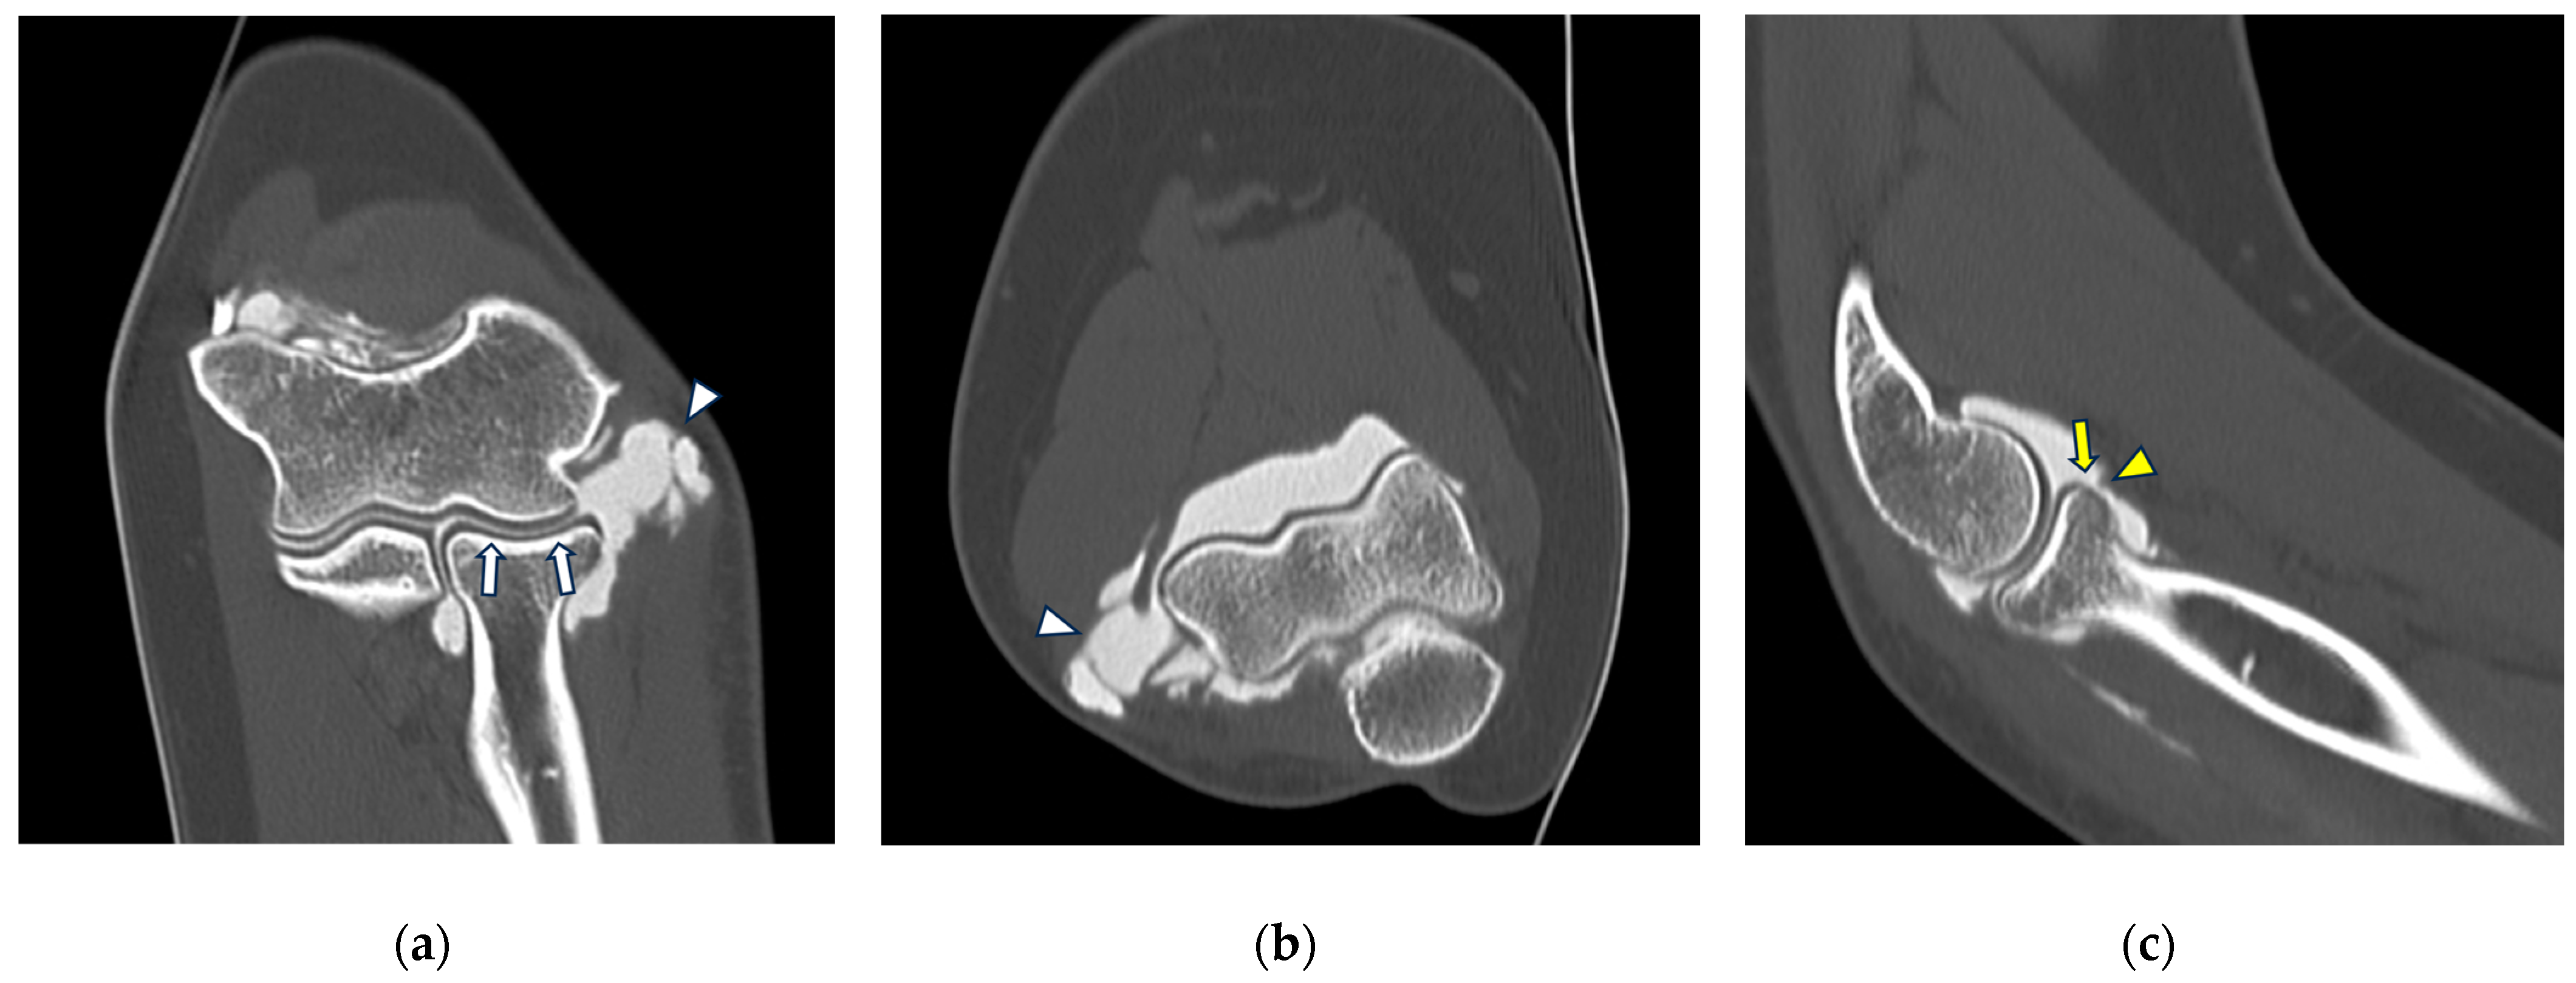

Figure 3.

CT arthrography of a patient with chronic elbow instability. (a) Sagittal image shows pitting and fissuring of radial head cartilage, involving >50% of its thickness (grade III) (white arrows); (b) coronal reformat of the same patient shows a focal full-thickness cartilage defect of the anteromedial radial head (grade IV) (white arrow). In the same image, mature calcifications can be seen at the insertion of the common extensor tendon (white arrowhead).

Figure 4.

CT-arthrography of a patient with rheumatoid arthritis. (a) Sagittal image shows pathological widening of the anterior humero-ulnar recess (asterisk), osteophytosis of the coronoid process (white arrowhead) and a distended posterior recess containing multiple non-calcific loose bodies compatible with secondary synovial chondromatosis (yellow arrowheads); (b) coronal image shows abnormal morphology and complete chondral erosion of both the radial head dish and lateral humeral condyle (yellow arrows).